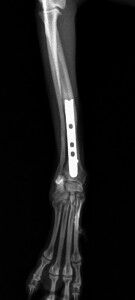

こんばんは、フジタどうぶつ病院です。今日はトイ・プードルの橈尺骨骨折の治療についてご報告させて頂きます。トイ・プードルは脚が長く、骨が細いので非常に骨折が多い犬種です。椅子やソファーから降りた時に折れたり、中には飼い主さんの後ろを歩いていて気づいたら脚を挙げていて病院でレントゲンを撮ったら折れていた、ということもあるようです。今回の症例報告のワンちゃんは椅子から降りた時に折れてしまったようです。下の写真が病院に来院時に撮ったレントゲン写真です。前脚の橈骨と尺骨が折れています。

治療はプレートで固定する方法を行いました。骨折位置が橈骨先端に比較的近い位置だったことと、トイ・プードルは骨の増生が悪いことで有名なので少し気を遣う症例でした。プレートはステンレスプレートを用いました。手術直後が下の写真です。